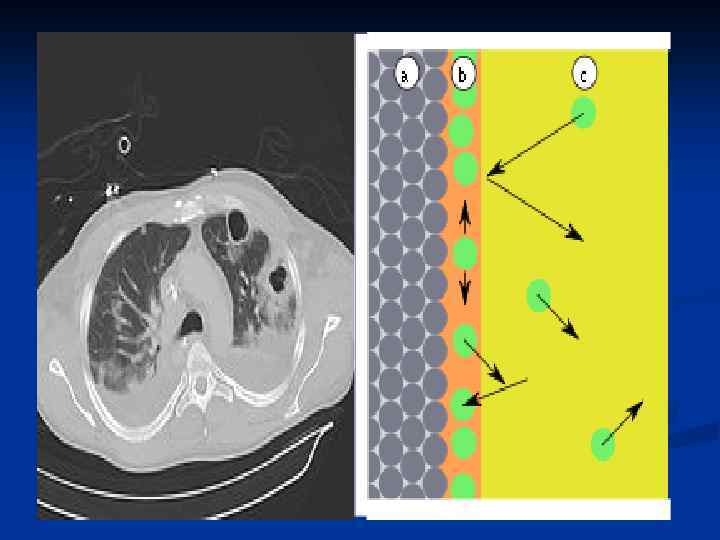

n Гемосорбцияны қандағы әр түрлі зиянды заттардан тазарту үшін қолданады. Ағзада әдетте бұл бауырдың жұмысы. «Гемо» -қан, «сорбция» -ағзаны уландырушы зиянды заттардан тазарту, яғни қанды, қан сары суын, лимфаны токсиндерден, улы заттардан тазарту үшін сорбентпен толтырылған арнаулы түтік арқылы сүзгіден өткізілуі.